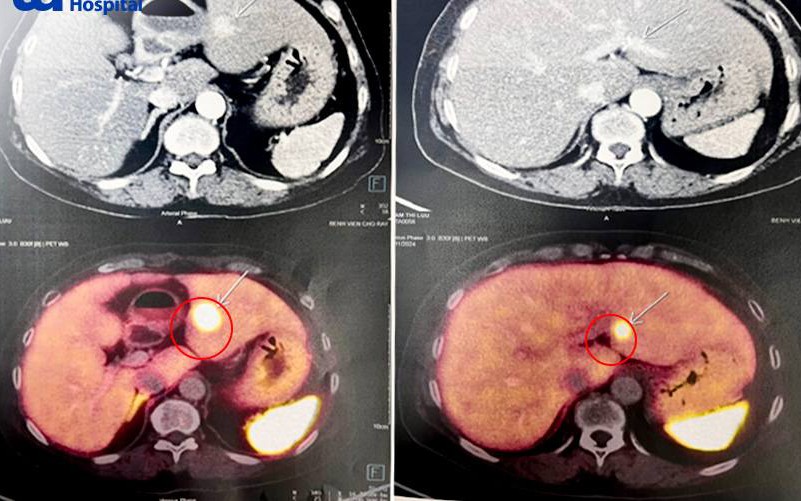

Mệt mỏi, sụt cân, người phụ nữ 65 tuổi đi khám phát hiện nổi u khắp người, tiến triển di căn ganGĐXH - Điều đáng lo ngại nhất của người bệnh này là đa u tuyến nội tiết tiến triển đã di căn gan, tiên lượng còn rất dè dặt và cần theo dõi sát.